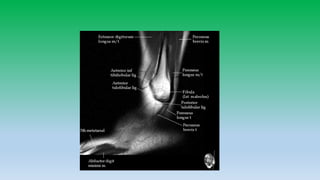

Lateral ankle tendon:

• Peroneus brevis and peroneus longus tendons pass posterior and

inferior to lateral malleolus in the retro-malleolar groove.

• Peroneus brevis is flatter and broader lies anterior to longus, whereas

peroneus longus is posteriolateral and is more rounded. Peroneal

tendons are held inplace by superior retinaculum.

• Split tears are common in brevis.

• Peroneal tendons can sublux or dislocate , whenever there is tear of

superior retinaculum. Diagnosis is made if tendons are located lateral

to distal fibula rather than posterior to it. Hypoplastic retromalleolar

groove can predispose to subluxation.